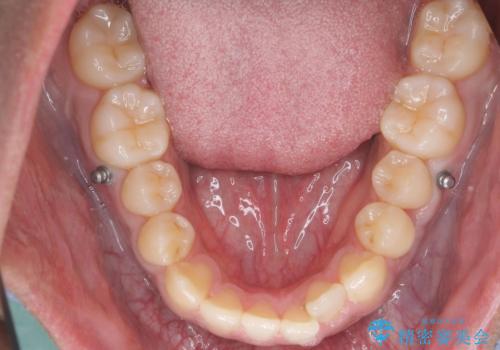

骨格性の受け口だったため、矯正用のミニスクリューを用いて、下の前歯をしっかり内側に入れました。

また、下顎はミニスクリューからマウスピースにゴムをかけて、下の歯並びが前に出ないようにして並べています。